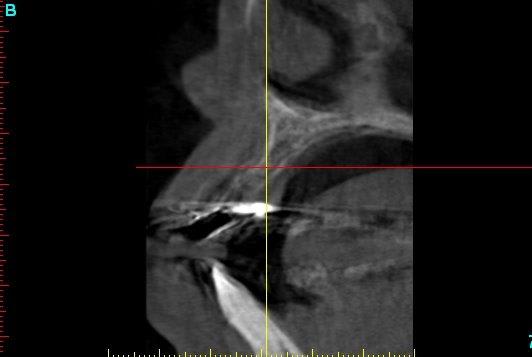

un autre petit cas courant, agénésie 12/22